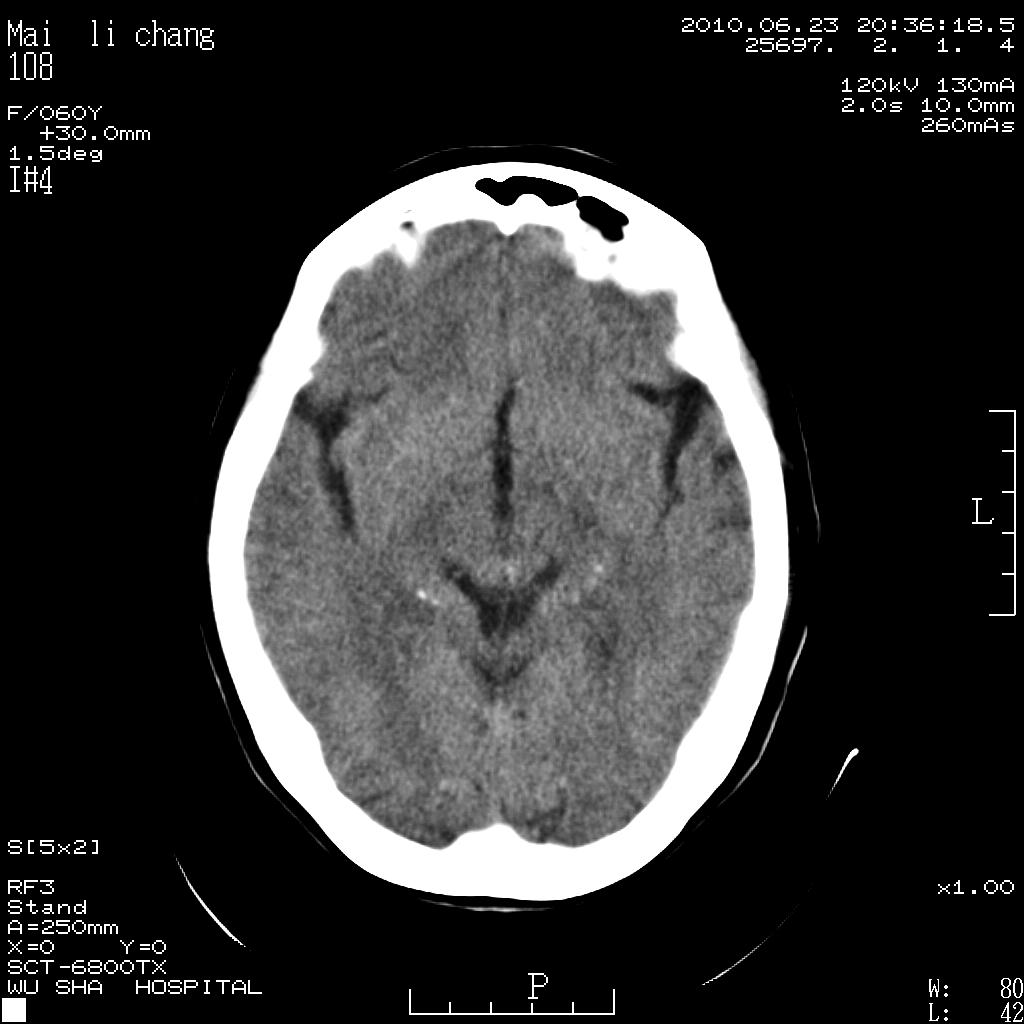

女性,60岁,右手无力一天

脑梗塞?并皮层下动脉硬化性脑病?还需要考虑什么?请大家指导,先谢了。

左侧基底节区及放射冠区多发脑梗塞。

左侧基底节区及侧脑室旁多发脑梗塞

左侧基底节区腔隙性脑梗塞。

2.左侧基底节区可见片状低密度病灶。

意见考虑脑梗塞。

左侧基底节及放射冠区脑梗塞。